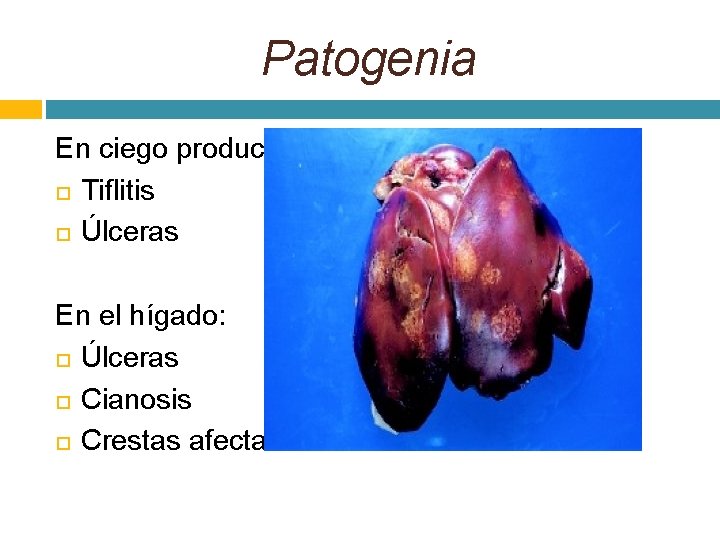

Patogenia En ciego produce: Tiflitis Úlceras En el hígado: Úlceras Cianosis Crestas afectadas

Lesiones Las lesiones son en la mucosa cecal y en el tejido hepático pueden ser aprovechadas por agentes patógenos oportunistas como E. coli y los coccidios.

Diagnóstico Debe ser asertivo en una coprología con heces frescas. También pueden ser por necropsia, al ver las lesiones típicas en el ciego y el hígado.